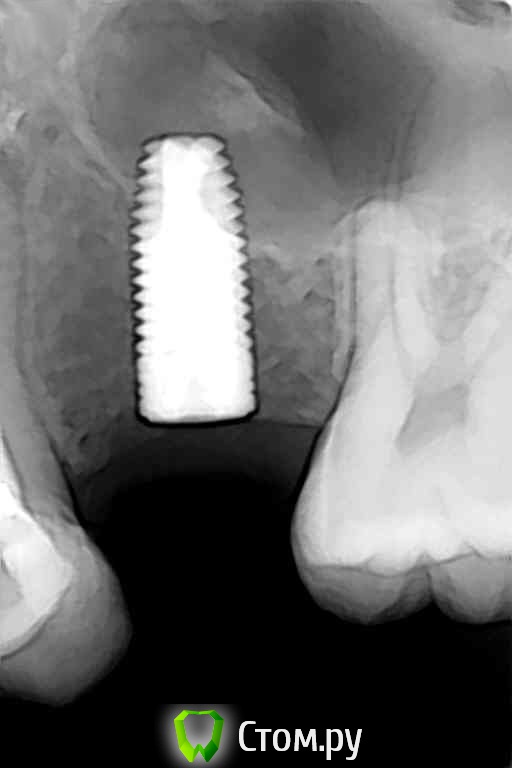

Михаил Демурчян Опубликовано 29 октября, 2014 Поделиться Опубликовано 29 октября, 2014 (изменено) Комментарии к фотографиям: 1. В тех случаях, когда нужно поднять пазуху всего на 2-3 мм, можно обойтись совершенно без остеопластического материала. Рентгенограмма до операции. 2. Рентгенограмма сразу после операции. Над установленным имплантатом виден фрагмент кости вследствие проведенной остеотомии. Тень полусферы обозначает границы кровяного сгустка под слизистой оболочкой пазухи. 3. Контрольный снимок спустя год после операции. Видна новая граница пазухи над имплантатом. Изменено 29 октября, 2014 пользователем Михаил Демурчян 4 Ссылка на комментарий